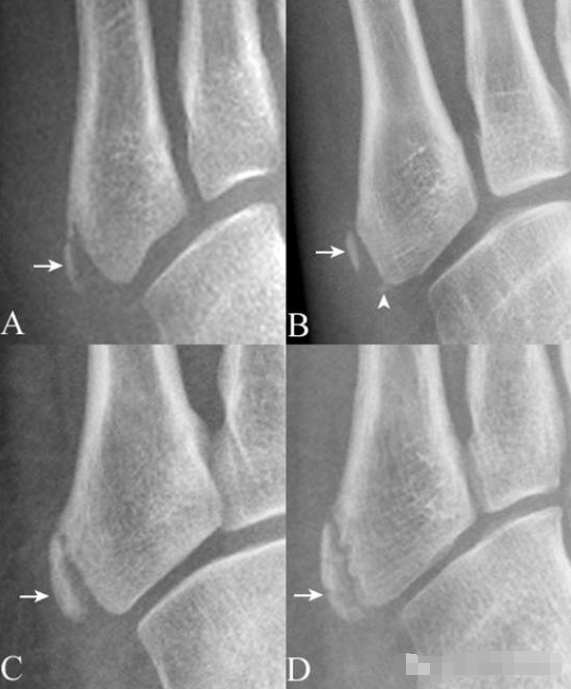

16.第5跖骨粗隆骨化中心:

第5跖骨粗隆骨化中心(箭),形态多样,A(女,10岁)为线样且不连续,B(男,13岁)为多发(箭与箭头),C(男,12岁)为边缘光整,D(男,11岁)为内缘粗糙伴裂隙。需与撕脱骨折鉴别,其与粗隆长轴近似平行,而撕脱骨折为腓骨短肌肌腱牵拉所致,骨折线多为横行。